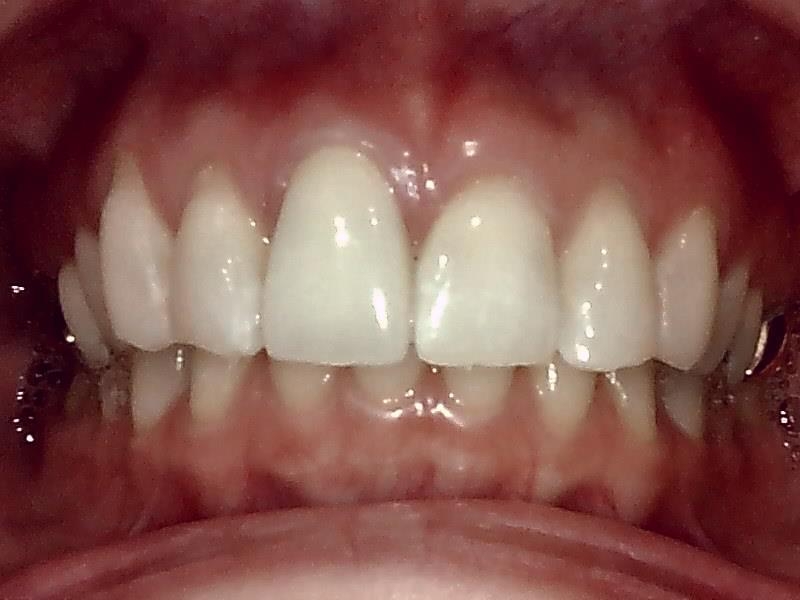

写真; ジルコニアセラミック冠装着

完成